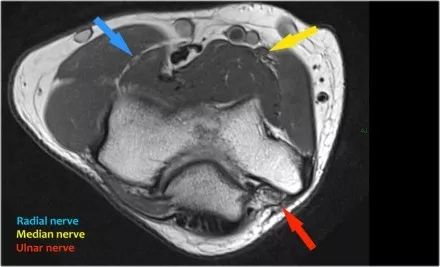

桡神经:在桡骨头水平可以最好地识别桡神经,在那里你可以看到桡骨隧道中的浅表和深支(箭头)。这是寻找桡神经的非常一致的地方。

深分支形成后骨间神经,穿过Frohse拱门(箭头)的旋后肌。